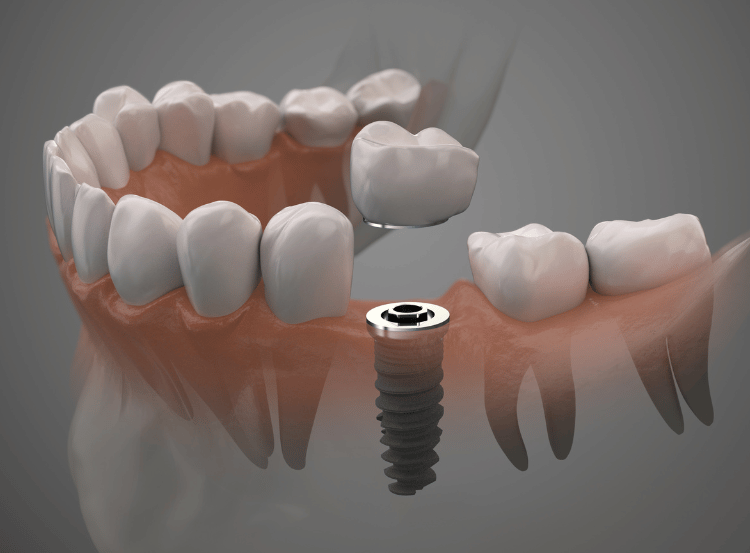

Unlike removable options, single tooth implants are fixed into the jaw and designed to last many years. They provide a stable foundation so there’s no slipping or movement.

By replacing the missing tooth root, implants help maintain bone density and prevent neighbouring teeth from shifting. Unlike traditional bridges, they do not require drilling into healthy teeth.

The ceramic crown is custom-made to match the shape, size, and shade of your natural teeth. The implant functions like a real tooth, allowing you to eat, chew, and speak with confidence, and it can be maintained with regular brushing, flossing, and dental check-ups.

The titanium implant is carefully placed into the jaw under local anaesthetic. If the natural tooth is still present, it will be extracted first. For nervous patients, sedation can also be provided.

Once healed, an impression is taken to design a bespoke crown that blends seamlessly with your smile. The crown is then securely attached to the implant, restoring your bite and appearance. From start to finish, treatment usually takes around six to eight months, depending on healing time.